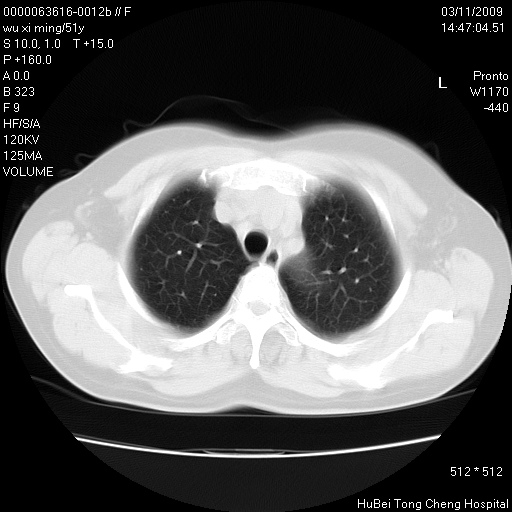

患者 女,51岁。因“胆囊炎,胆囊结石”,行常规术前胸部x线检查发现:右上肺结节病灶,建议行进一步检查。患者无咳嗽、咳痰及咯血等呼吸道症状,近期出现背部疼痛不适。

胸部ct轴位平扫(层厚10mm,螺距1.5,重建间隔10mm;部分层面:层厚3mm,螺距1.0,重建间隔3mm),图像如下:

右肺周围型肺癌伴肺内转移信胸椎转移

1、周围型肺癌。(毛刺正、血管束集征,分叶。)

集束征,胸膜牽拉征,毛刺,淺分葉高度提示ca.

右肺周围型肺癌伴肺内转移及胸椎转移。已无手术机会。